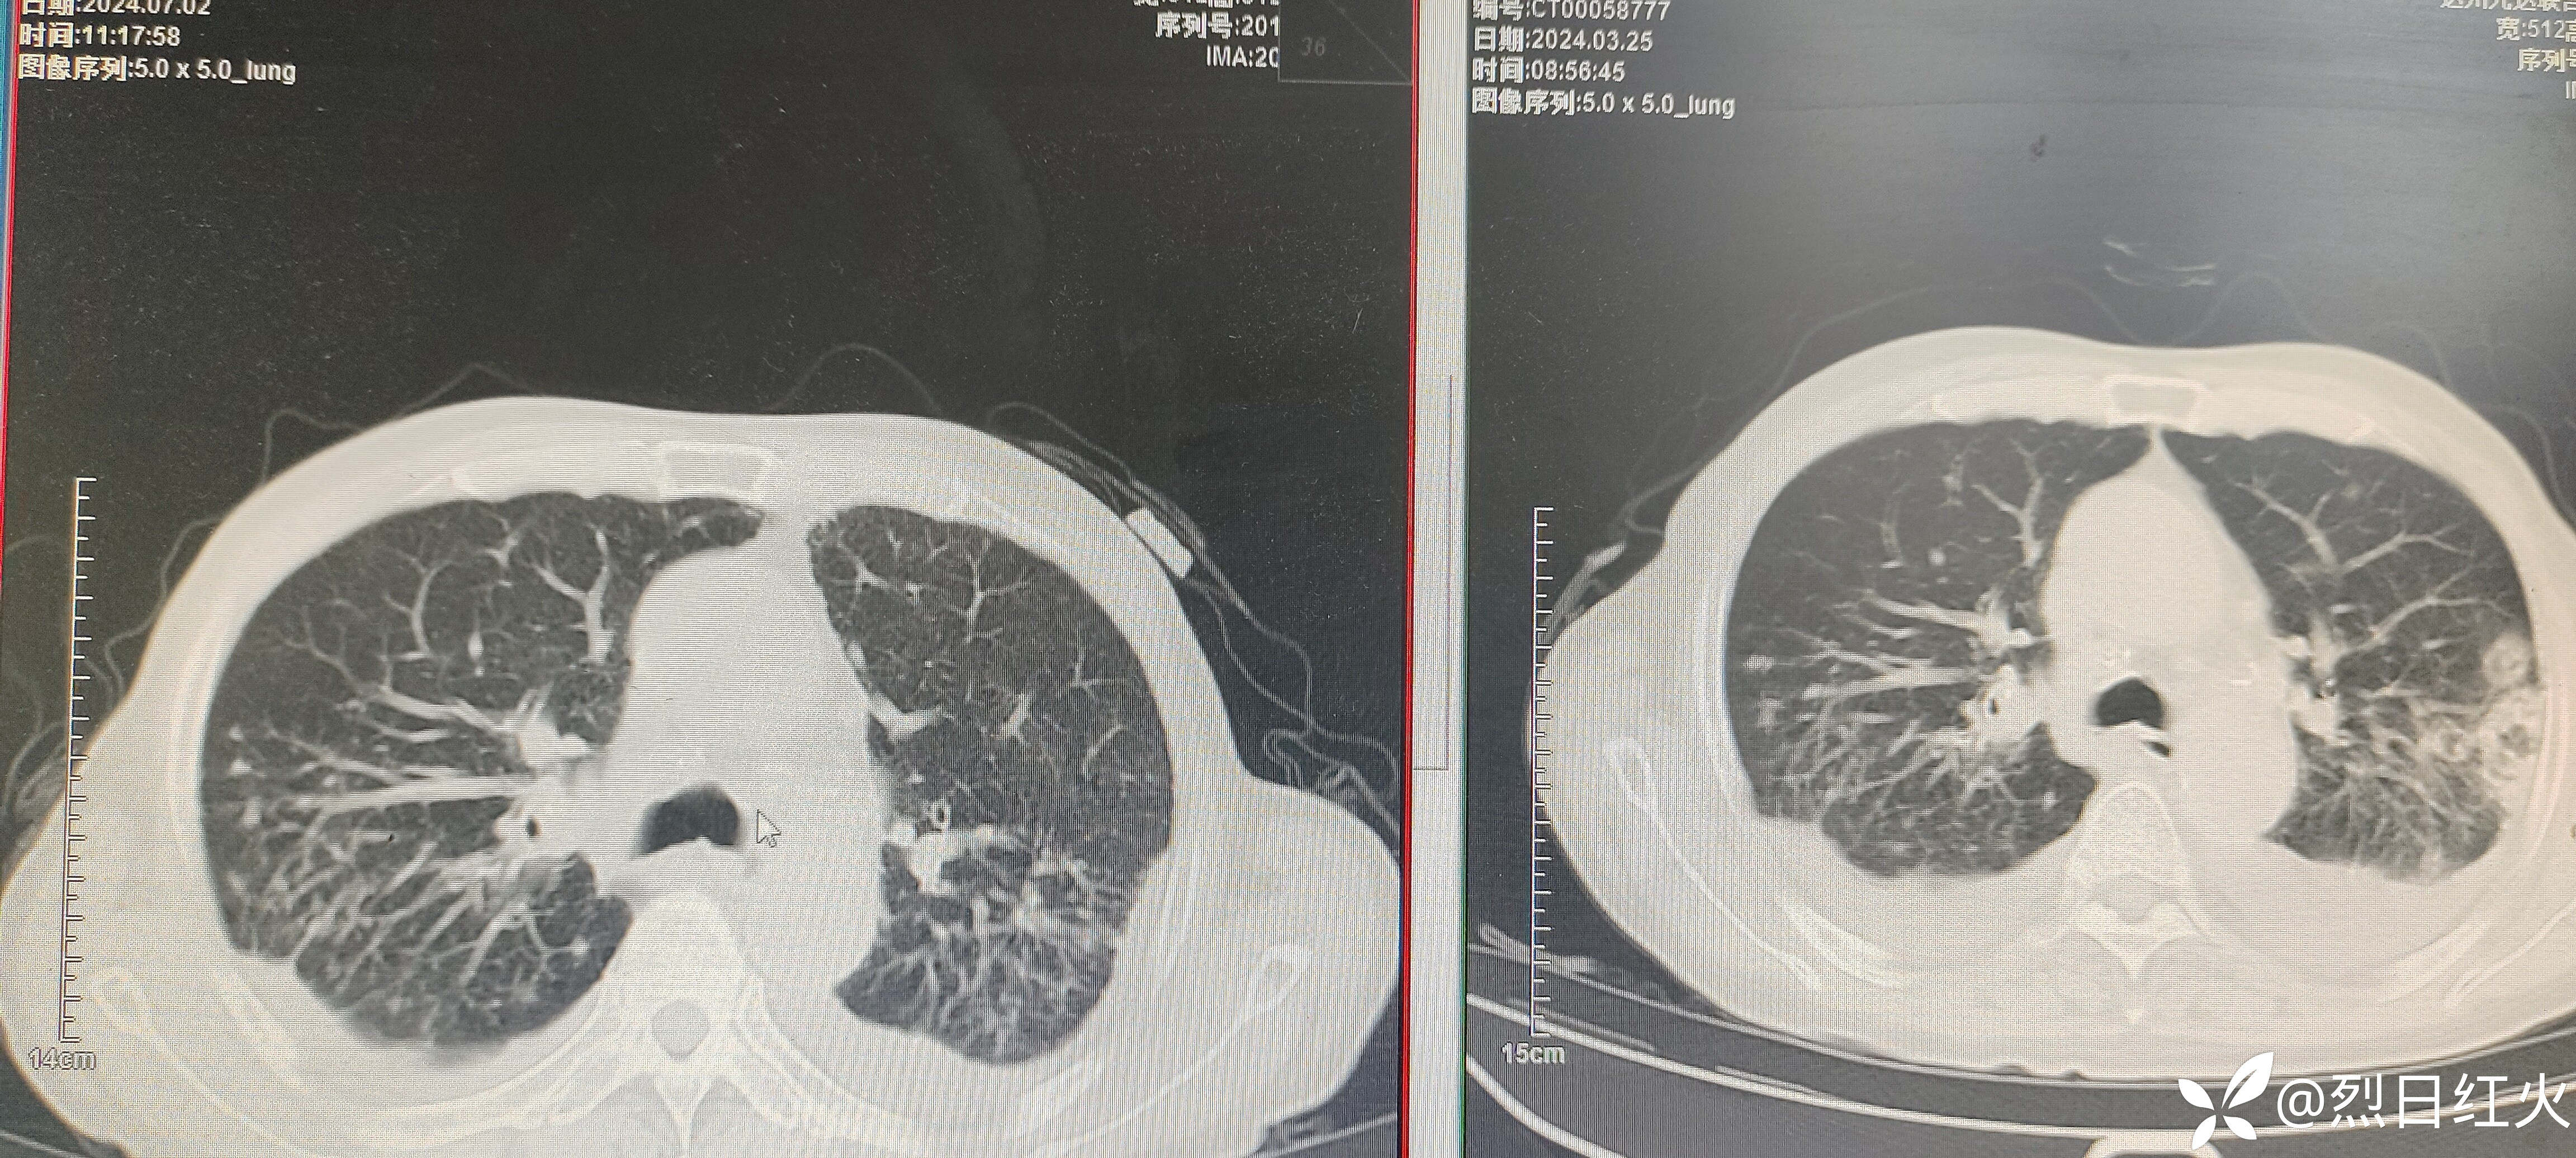

该病历患者入院后病情缓解,以后症状逐渐加重,治疗经过有不足之处望指正!2024-07-02复查胸部CT与2024-03-25胸部CT对比,病灶较前明显吸收。如下图:

患者经伏立康唑抗真菌治疗后症状及影像上均得到改善!目前出现面部,双手(裸露皮肤)发黑。考虑伏立康唑药物不良反应导致皮肤变色,光反应。鉴于患者情况是否停抗真菌药,还是继续当前剂量服用,或者减量服用,如减量减多少?请各位大咖,各位考师指点,谢谢!